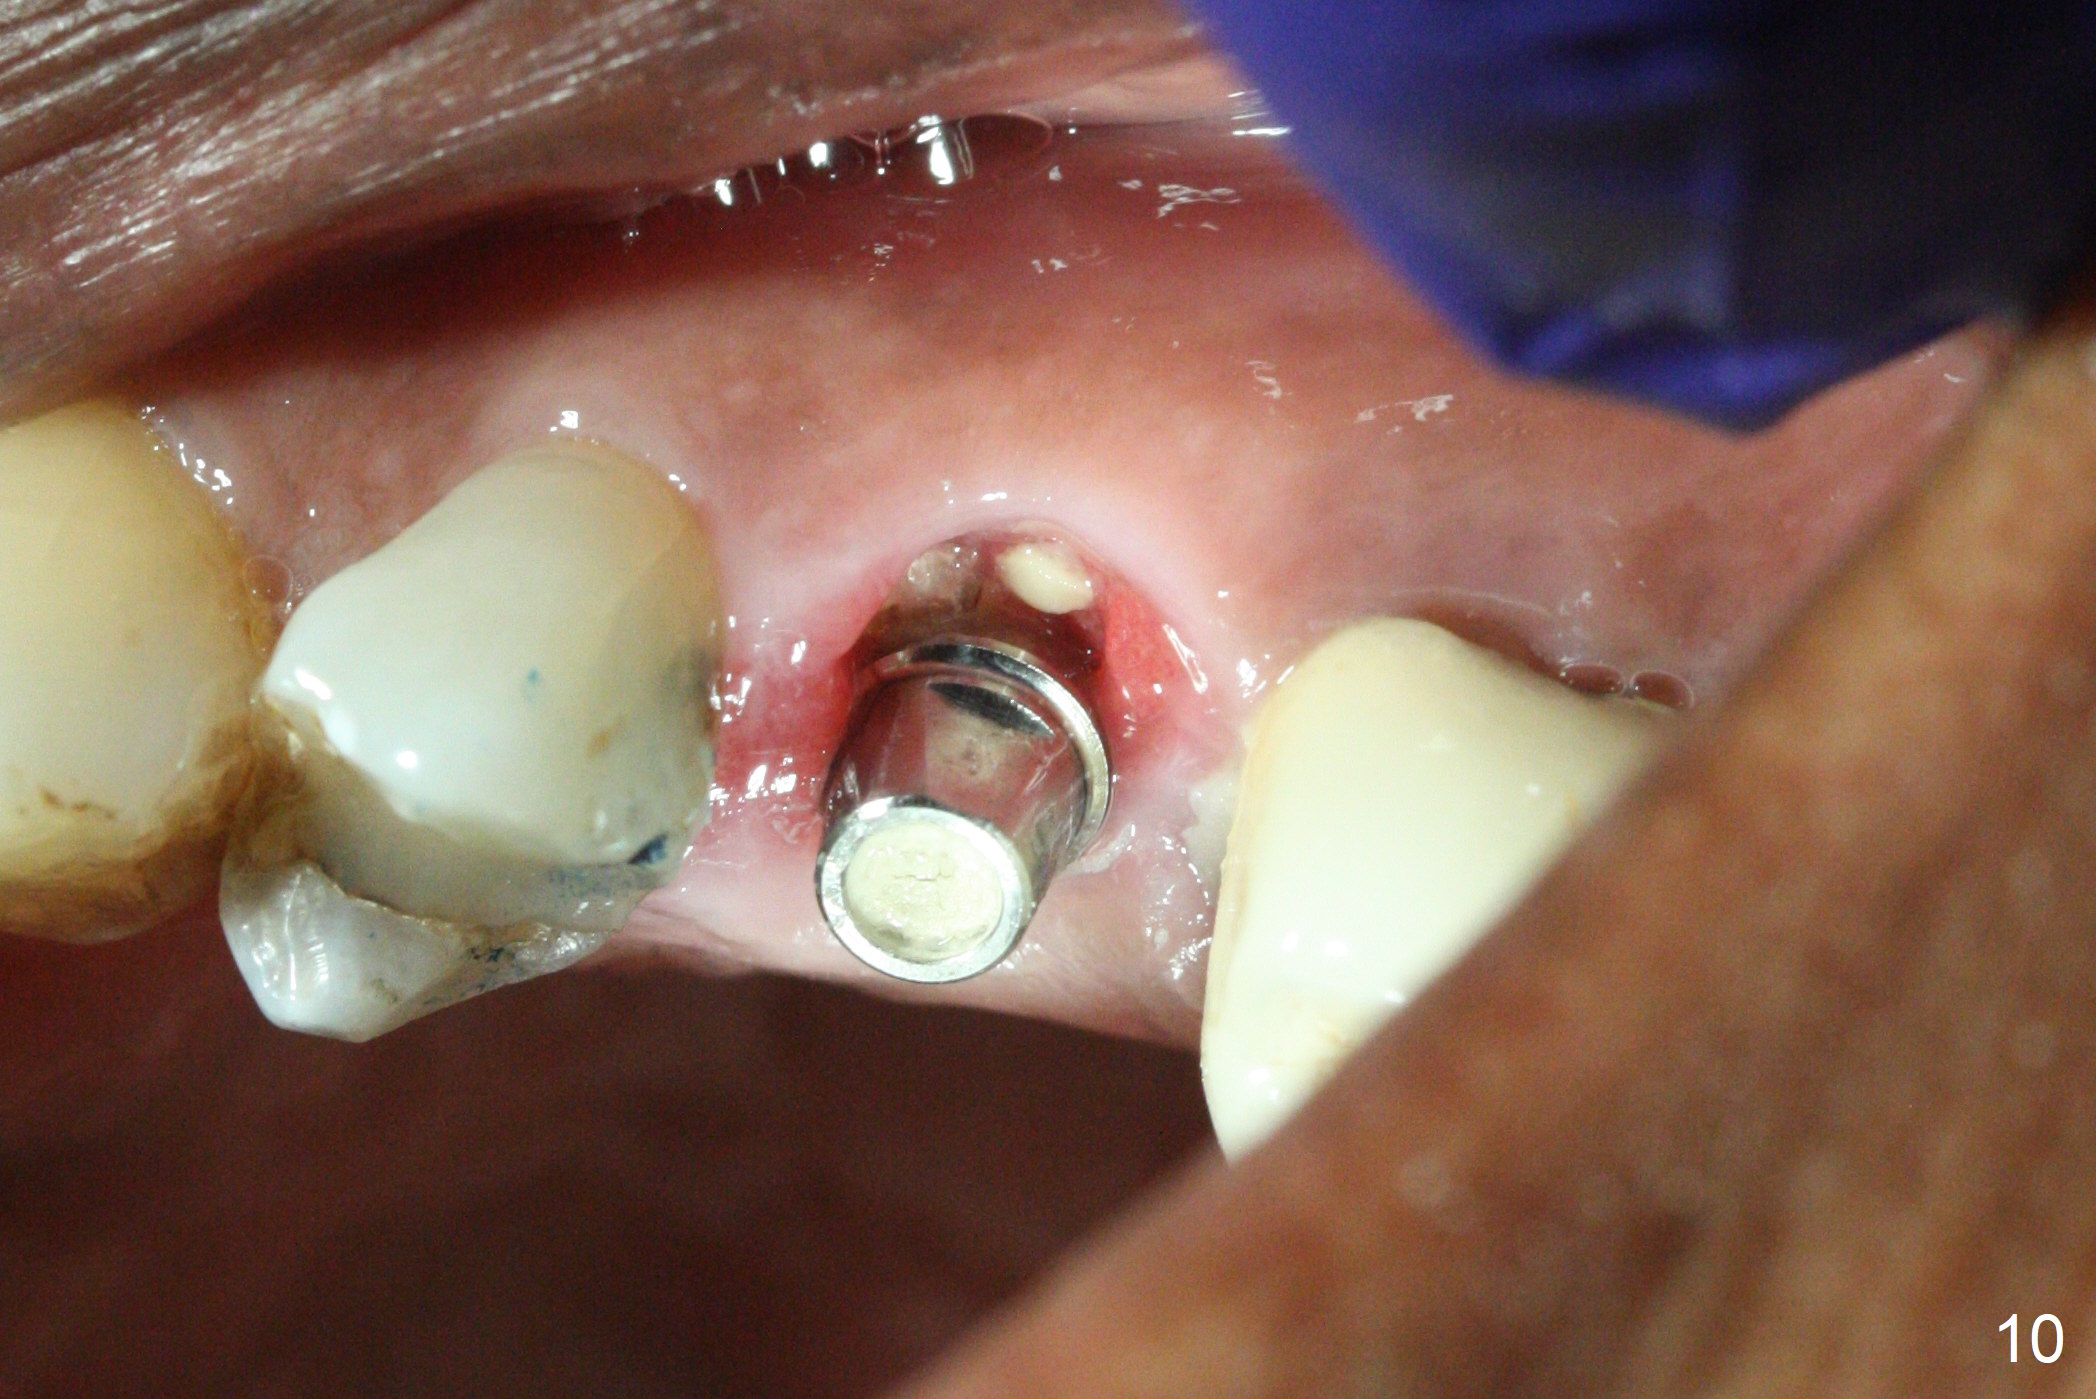

Since the apical native bone is limited at #13 after extraction, no PA is taken until a 4x11 mm dummy implant is placed after 1.6 mm and 3.3 mm drills for 13 mm (Fig.1). After using Lindamann bur to move the osteotomy distal and reusing 3.3 mm drill, the trajectory of a 4.5x11 mm IBS dummy implant improves (Fig.2,3 with low stability). When the implant is removed, the buccal portion of the socket is found to be perforated (Fig.4 P). Although the reason for the perforation is unknown, it is repaired by insertion of a piece of PRF plug, followed by allograft. #1 and 2 in Fig.4 represent the 1st and 2nd osteotomies, as shown in Fig.1 and 2, respectively. The trajectory of the final 5x13 mm implant is acceptable (Fig.5-7, different angulations), so is insertion torque (45 Ncm). After placing a 5.5x4(4) mm abutment, an immediate provisional is fabricated (Fig.8 P) with occlusal clearance (*). The interdental papillae remain in place 12 days postop (Fig.9 *). There is no sign of postop sinus infection. The provisional is loose 18 days postop; the abutment is changed to 5x4(3) mm (Fig.10). It is difficult to catch the mesial margin of the abutment for impression 4 months postop, due to poor oral hygiene and the short cuff (3 mm, Fig.11). The appointment for impression is rescheduled with emphasis on oral hygiene and no wearing the provisional for a few days prior to next appointment. Bone has grown into the space between the 1st and 2nd threads 5 months post cementation (Fig.12) and the bone is normal, solid and dense 2 years 11 months post cementation (Fig.13 >). There is mesial open margin of the tooth #14 (Fig.13,14 *).